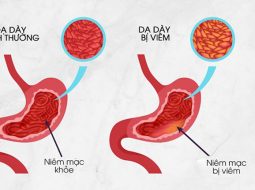

Trong Y học cổ truyền, xuất huyết dạ dày không đơn thuần là tổn thương cơ học mà là sự mất cân bằng trầm trọng giữa tỳ vị – can khí và khí huyết.

- Tỳ khí hư không sinh huyết, không thống nhiếp huyết, khiến huyết tràn ra ngoài mạch, sinh chảy máu.

- Can khí uất kết hóa hỏa, thiêu đốt vị âm, gây tổn thương mạch lạc dạ dày.

- Thực tích ứ trệ gây nhiệt hóa huyết, làm huyết đi loạn, mất kiểm soát.

Bởi vậy, Đông y không chỉ tìm cách cầm máu, mà phải giải quyết từ gốc: kiện tỳ, điều can, hòa vị, dưỡng huyết và liễm huyết.